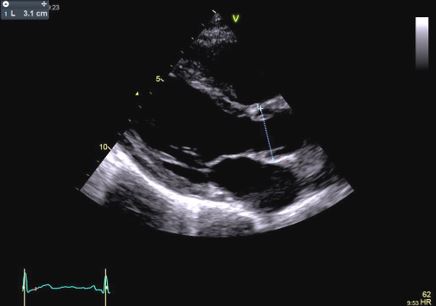

In our patient transthoracic echocardiography revealed normal diameters of the left ventricle with mild septal hypertrophy (EDD: 51 mm; ESD: 31 mm; IVS: 12 mm; PW 10 mm) with mild enlargement of the right ventricle (mid-cavity diameter: 37 mm), with normal biventricular systolic function. However, TTE revealed a tricuspid aortic valve with dilatation of the aortic root (44 mm, Z-score >2: Z=4.2). Ascending Aorta and aortic arch diameters were normal in absolute values (35 mm and 32 mm, respectively) and when keeping into consideration body size.

After a year, our patient underwent TTE that showed an aortic root dimension of 44 (Figure C), stable in comparison with the previous evaluation, with no modification of ascending aorta measurement and no LV enlargement (Figure A and B). He continues with yearly follow-up, continuing with personalized physical activity previously prescribed.